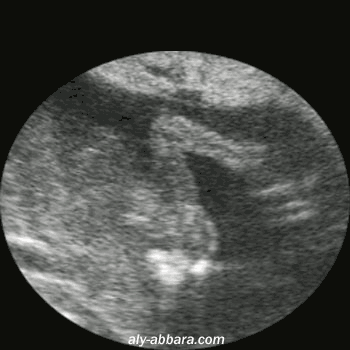

Aspect échographique de l'omoplate fœtale

Coupe frontale

Il s'agit d'une grossesse à 17 semaines d'aménorrhée